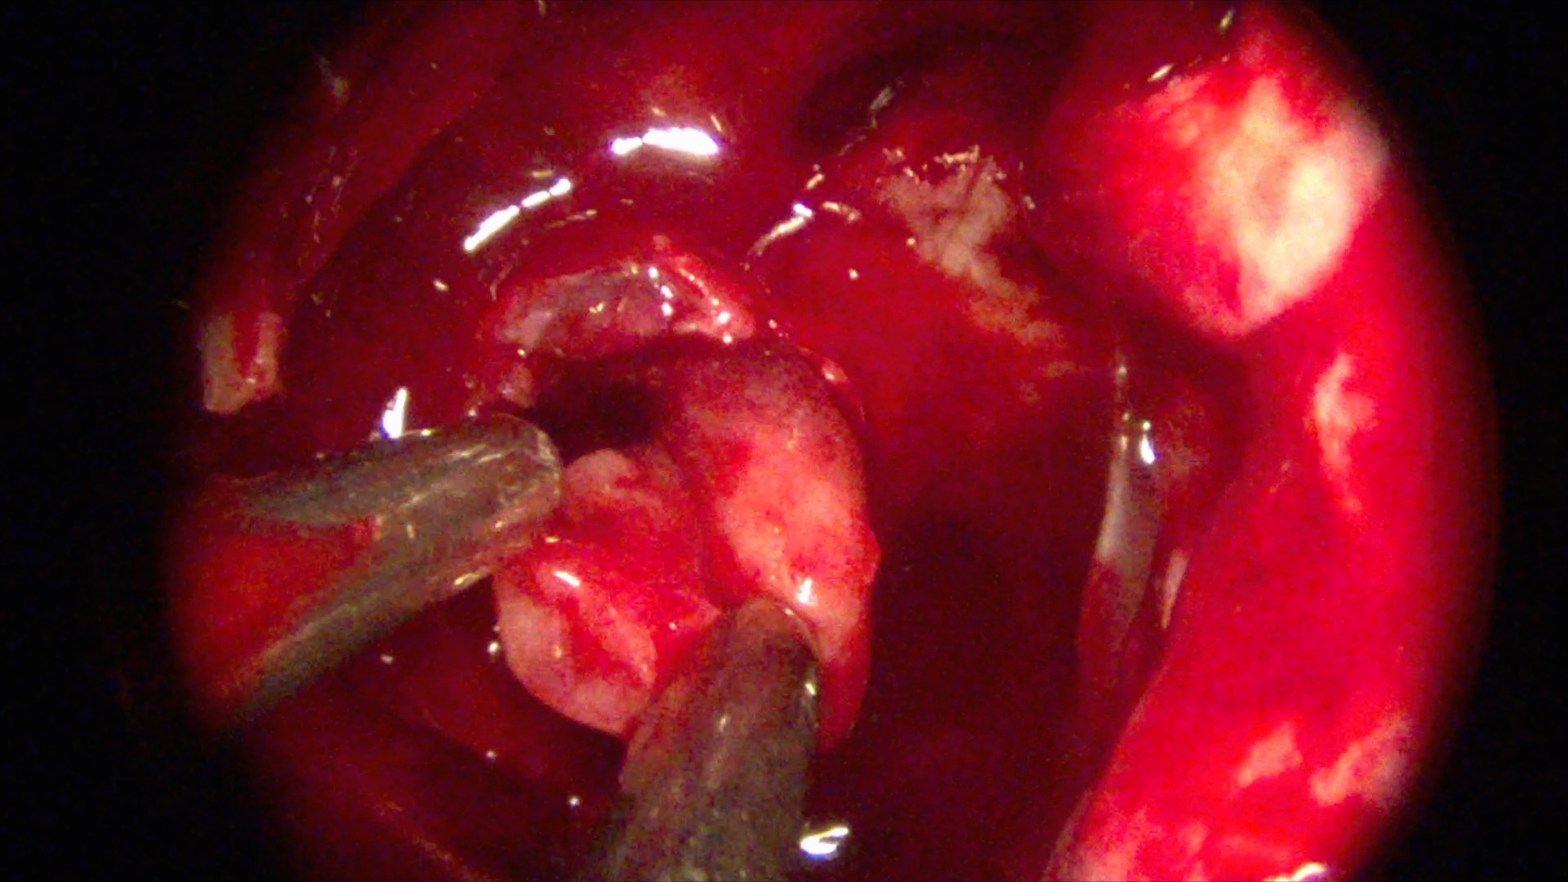

Interesting Cases

Among the hundreds of cases that I have done in Kenya so far, these few stood out. This patient had a glomus jugulare tumor, which is a tumor that arises from the skull base where the jugular vein exits the brain. The former ENT here removed the tumor a few years ago in a majorContinue reading "Interesting Cases"